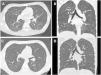

Se describe el caso de un adolescente de 17 años que ingresa por insuficiencia respiratoria aguda grave junto con hipoxemia. Durante su estancia se realizaron numerosas pruebas complementarias siendo los hallazgos en la tomografía computarizada pulmonar imprescindibles para el diagnóstico; en ella se aprecian micronódulos en vidrio deslustrado con patrón de árbol en brote de distribución difusa1 (fig. 1).

Imágenes de tomografía computarizada durante su ingreso. Las imágenes axiales (A y B) y coronales (C y D) muestran pequeñas opacidades micronodulares con patrón de árbol en brote distribuidos de forma difusa, con región subpleural respetada. En las imágenes B y D se evidencian focos consolidativos en LID.